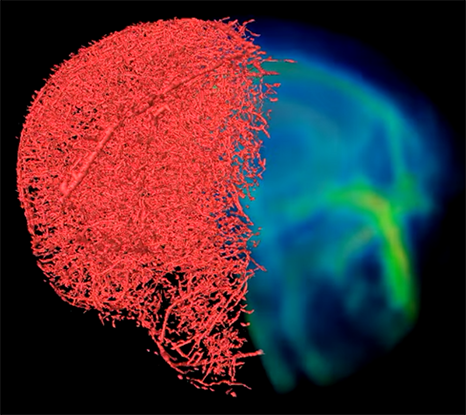

Esta técnica se basa en una combinación de agentes poliméricos que se pueden difundir en ese conjunto de vasos sanguíneos y conseguir así, obtener imágenes mediante microscopía óptica, resonancia magnética y tomografía computarizada (TC). La imagen combinada de estas técnicas crea mapas de tejido altamente detallados en diferentes escalas espaciales, consiguiendo información sobre los tipos de células y las estructuras de tejido que rodean los vasos sanguíneos.

El nombre del contraste que permite la obtención de imágenes de la misma muestra mediante los tres tipos de imágenes es VascuViz. Los componentes de este son un agente de contraste fluorescente para MRI llamado galbúmina-rodamina y un agente de contraste para TC llamado BriteVu. La mezcla de los polímeros permite obtener imágenes tanto de la microvasculatura como de la macrovasculatura.

Por último Akanksha Bhargava trata la importancia de este avance que permite ensamblar las visualizaciones complejas de los vasos sanguíneos. “Ahora, en lugar de usar una aproximación, podemos estimar con mayor precisión características como el flujo sanguíneo en los vasos sanguíneos reales y combinarlo con información complementaria, como la densidad celular”, concluye la investigadora.